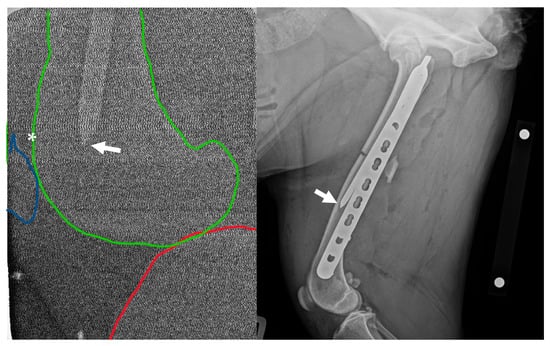

Post-operative mediolateral and craniocaudal radiographic projections were acquired. These images showed adequate reduction with appropriate fragment alignment. The distal screws and two proximal screws adjacent to the fracture were bicortical. The proximal two screws were unicortical, and the second screw was inserted past the IMP. The distal tip of the IMP was located approximately 50 mm proximal to the location, documented by intra-operative radiography (Figure 1).

Figure 1. Left: Intra-operative low-radiation mediolateral radiograph acquired using a hand-held dental X-ray unit. The distal tip of the intramedullary pin (arrow) is apparent at the level of the femoral metaphysis/base of patella (asterisk). The distal femur is outlined in green, the proximal tibia is outlined in red, and the patella is outlined in blue. Right: Initial post-operative mediolateral view showing insufficient purchase of the distal fragment with the intramedullary pin; the tip of the pin (arrow) is located in the distal-third of the diaphysis, approximately 50 mm proximal to the patella. NB a calibration marker is present, with a distance of 10 cm between the centre of the metal spheres.